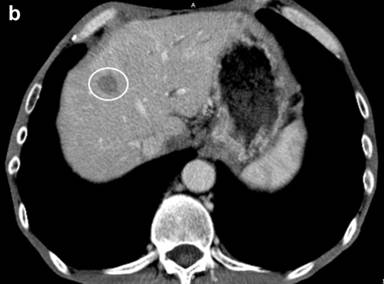

Figure 2. a. The contrast enhanced CT revealed newly found liver metastases (marked) suggestive of disease progression. b. The contrast enhanced CT image before HIFU showed a hypodense lesion of a liver metastasis about 14 mm in diameter in the right lobe (segment seven). c. Twelve months after the combination treatment with HIFU and chemotherapy the liver metastases were significantly reduced on the contrast control CT. |